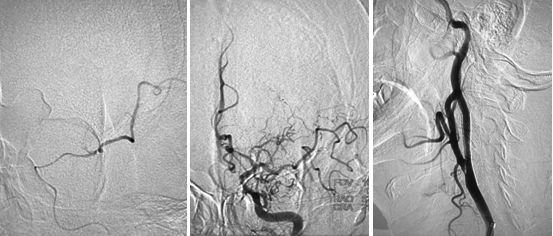

局麻下,将8F导引导管上行至颈总动脉远端,在路径途指导下,将微导丝(Transcend)、微导管(Echelon-10)通过颈内动脉狭窄段至C2段,造影证实微导管位于真腔内,颈内动脉末端闭塞,交换出微导管,沿导丝送入Maverick(2.0x20mm)球囊至狭窄处,予以扩张球囊,造影提示狭窄有所改善,导引导管上行困难,遂沿导丝送入Wallstent(9x30mm)支架至狭窄处,释放支架,造影提示残余狭窄率约为60%,遂沿导丝送入LitePAC (4.0x30mm)球囊至狭窄处予以后扩张,造影提示狭窄明显改善,将球囊半充盈状态,导引导管沿球囊越过支架支颈内动脉C1段远端,再次造影示颈内动脉末端仍然闭塞,(图6)

图6

在路径途指导下,将微导丝(Transcend)、微导管(Rebar 027)沿导引导管送至左侧大脑中动脉M2段,撤出微导丝,经微导管造影,造影证实微导管位于真腔内,大脑中动脉远端血管通畅,将取栓支架Solitaire AB (6x30mm) 送至血栓处,释放取栓支架,静置5分钟后取出支架,可见支架内大量血栓,复查造影提示左侧大脑前动脉、左侧大脑中动下干通畅,左侧前大脑前动脉可向左侧大脑中动脉代偿供血,(图7)此时患者右侧肢体无力症状明显好转,仍有不完全混合性失语,观察10分钟后复查造影提示血流仍然通畅,颈动脉支架处血流通畅,遂结束手术,继予以替罗非班抗栓治疗。

图7